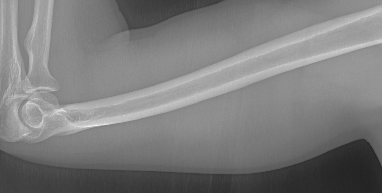

Refer to caption

(a) resolution 2044×1514204415142044\times 1514, run time 0.35s, α=1.34𝛼1.34\alpha=1.34

(b) resolution 2044×1514204415142044\times 1514, run time 0.35s, α=1.39𝛼1.39\alpha=1.39

(c) resolution 2044×1514204415142044\times 1514, run time 0.35s, α=1.63𝛼1.63\alpha=1.63

(d) resolution 2044×1514204415142044\times 1514, run time 0.35s, α=2.42𝛼2.42\alpha=2.42

(e) resolution 2044×1514204415142044\times 1514, run time 0.35s, α=2.31𝛼2.31\alpha=2.31

(f) resolution 2044×1514204415142044\times 1514, run time 0.35s, α=3.61𝛼3.61\alpha=3.61

(g) resolution 2044×1514204415142044\times 1514, run time 0.35s, α=3.02𝛼3.02\alpha=3.02

(h) resolution 2044×1514204415142044\times 1514, run time 0.35s, α=1.47𝛼1.47\alpha=1.47

(i) resolution 2044×1514204415142044\times 1514, run time 0.35s, α=2.11𝛼2.11\alpha=2.11

(j) resolution 2570×2040257020402570\times 2040, run time 0.58s, α=2.34𝛼2.34\alpha=2.34

Figure 10: From left to right in each panel: input X-ray images (left), our estimated soft tissue (middle) and estimated bone image (right). The resolution, running time of our algorithm and parameter α𝛼\alpha are provided. For these practical images, our method requires about half second to achieve the bone and soft tissue decomposition task in MATLAB language on a laptop. Higher performance can be achieved by C++ language on a better hardware.

In the third experiment, we applied our method on a hand X-ray image data set (RSNA), which contains more than 10,000 hand X-ray images. And the image has high resolution (usually larger than 1514×2044151420441514\times 2044). These images are collected from clinical applications. Therefore, we can apply our method on these practical images, showing the efficiency and effectiveness of our method on real high resolution images.

In each panel of Fig. 10, the input image (left) is decomposed into soft tissue (middle) and bone image (right) by our method. Although we only show the first ten images from the data set, the results for the rest images are similar.

The bone images have better image contrast since the parameter α1𝛼1\alpha\geq 1 is theoretically guaranteed. Such enhancement can also be directly told by radiologists. Such enhancement is good for bone diagnosis in practical applications.

Moreover, the running time of our method on such high resolution images is less than half second in the MATLAB language on a laptop. Therefore, it can achieve higher performance on a better hardware in real applications. If higher performance is required, our model can be solved by the parallel Laplace equation solver on a modern graphic process unit (GPU), which usually has thousands of cores.